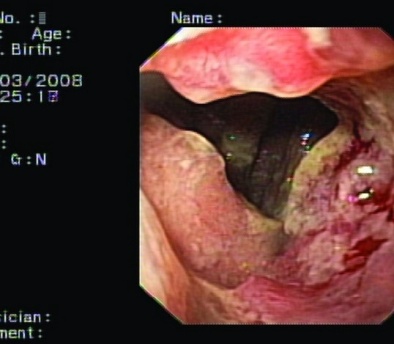

Upper gastrointestinal endoscopy showing a grossly deformed duodenal bulb. A steady trickle of bile was also seen to come from a slit-like orifice on the anterior duodenal wall suggestive of biliary duodenal fistula (green arrow)